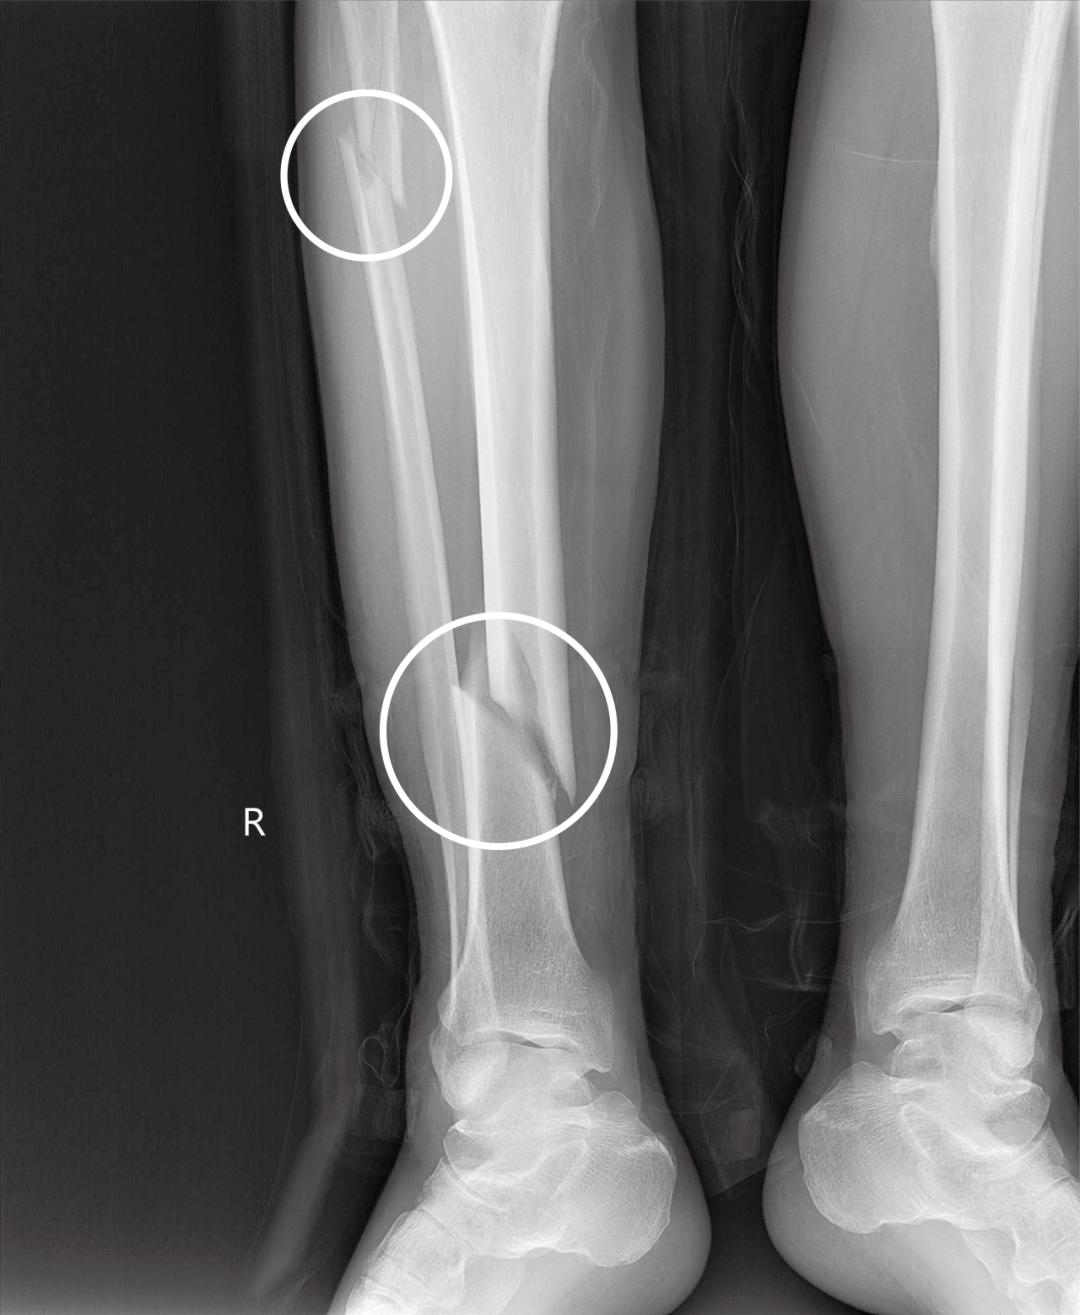

3月,顾老伯一场突如其来的车祸,被120送至奉城医院急诊骨科进行救治,接诊的刘宗海医生紧急安排了X线检查。

检查显示:胫骨下段粉碎骨折,右腓骨近端粉碎骨折

随即收治入院,由于胫腓骨都有骨折,引起腓总神经损伤,如果压迫时间久会造成神经的不可逆修复,黄淮医生评估病情后决定开展急诊手术。完善各项术前相关检查,各项指标均正常,经过详细的评估,骨科团队商讨后决定微创治疗,减少对患者身体的创伤,为顾老伯制定了周密的手术方案。